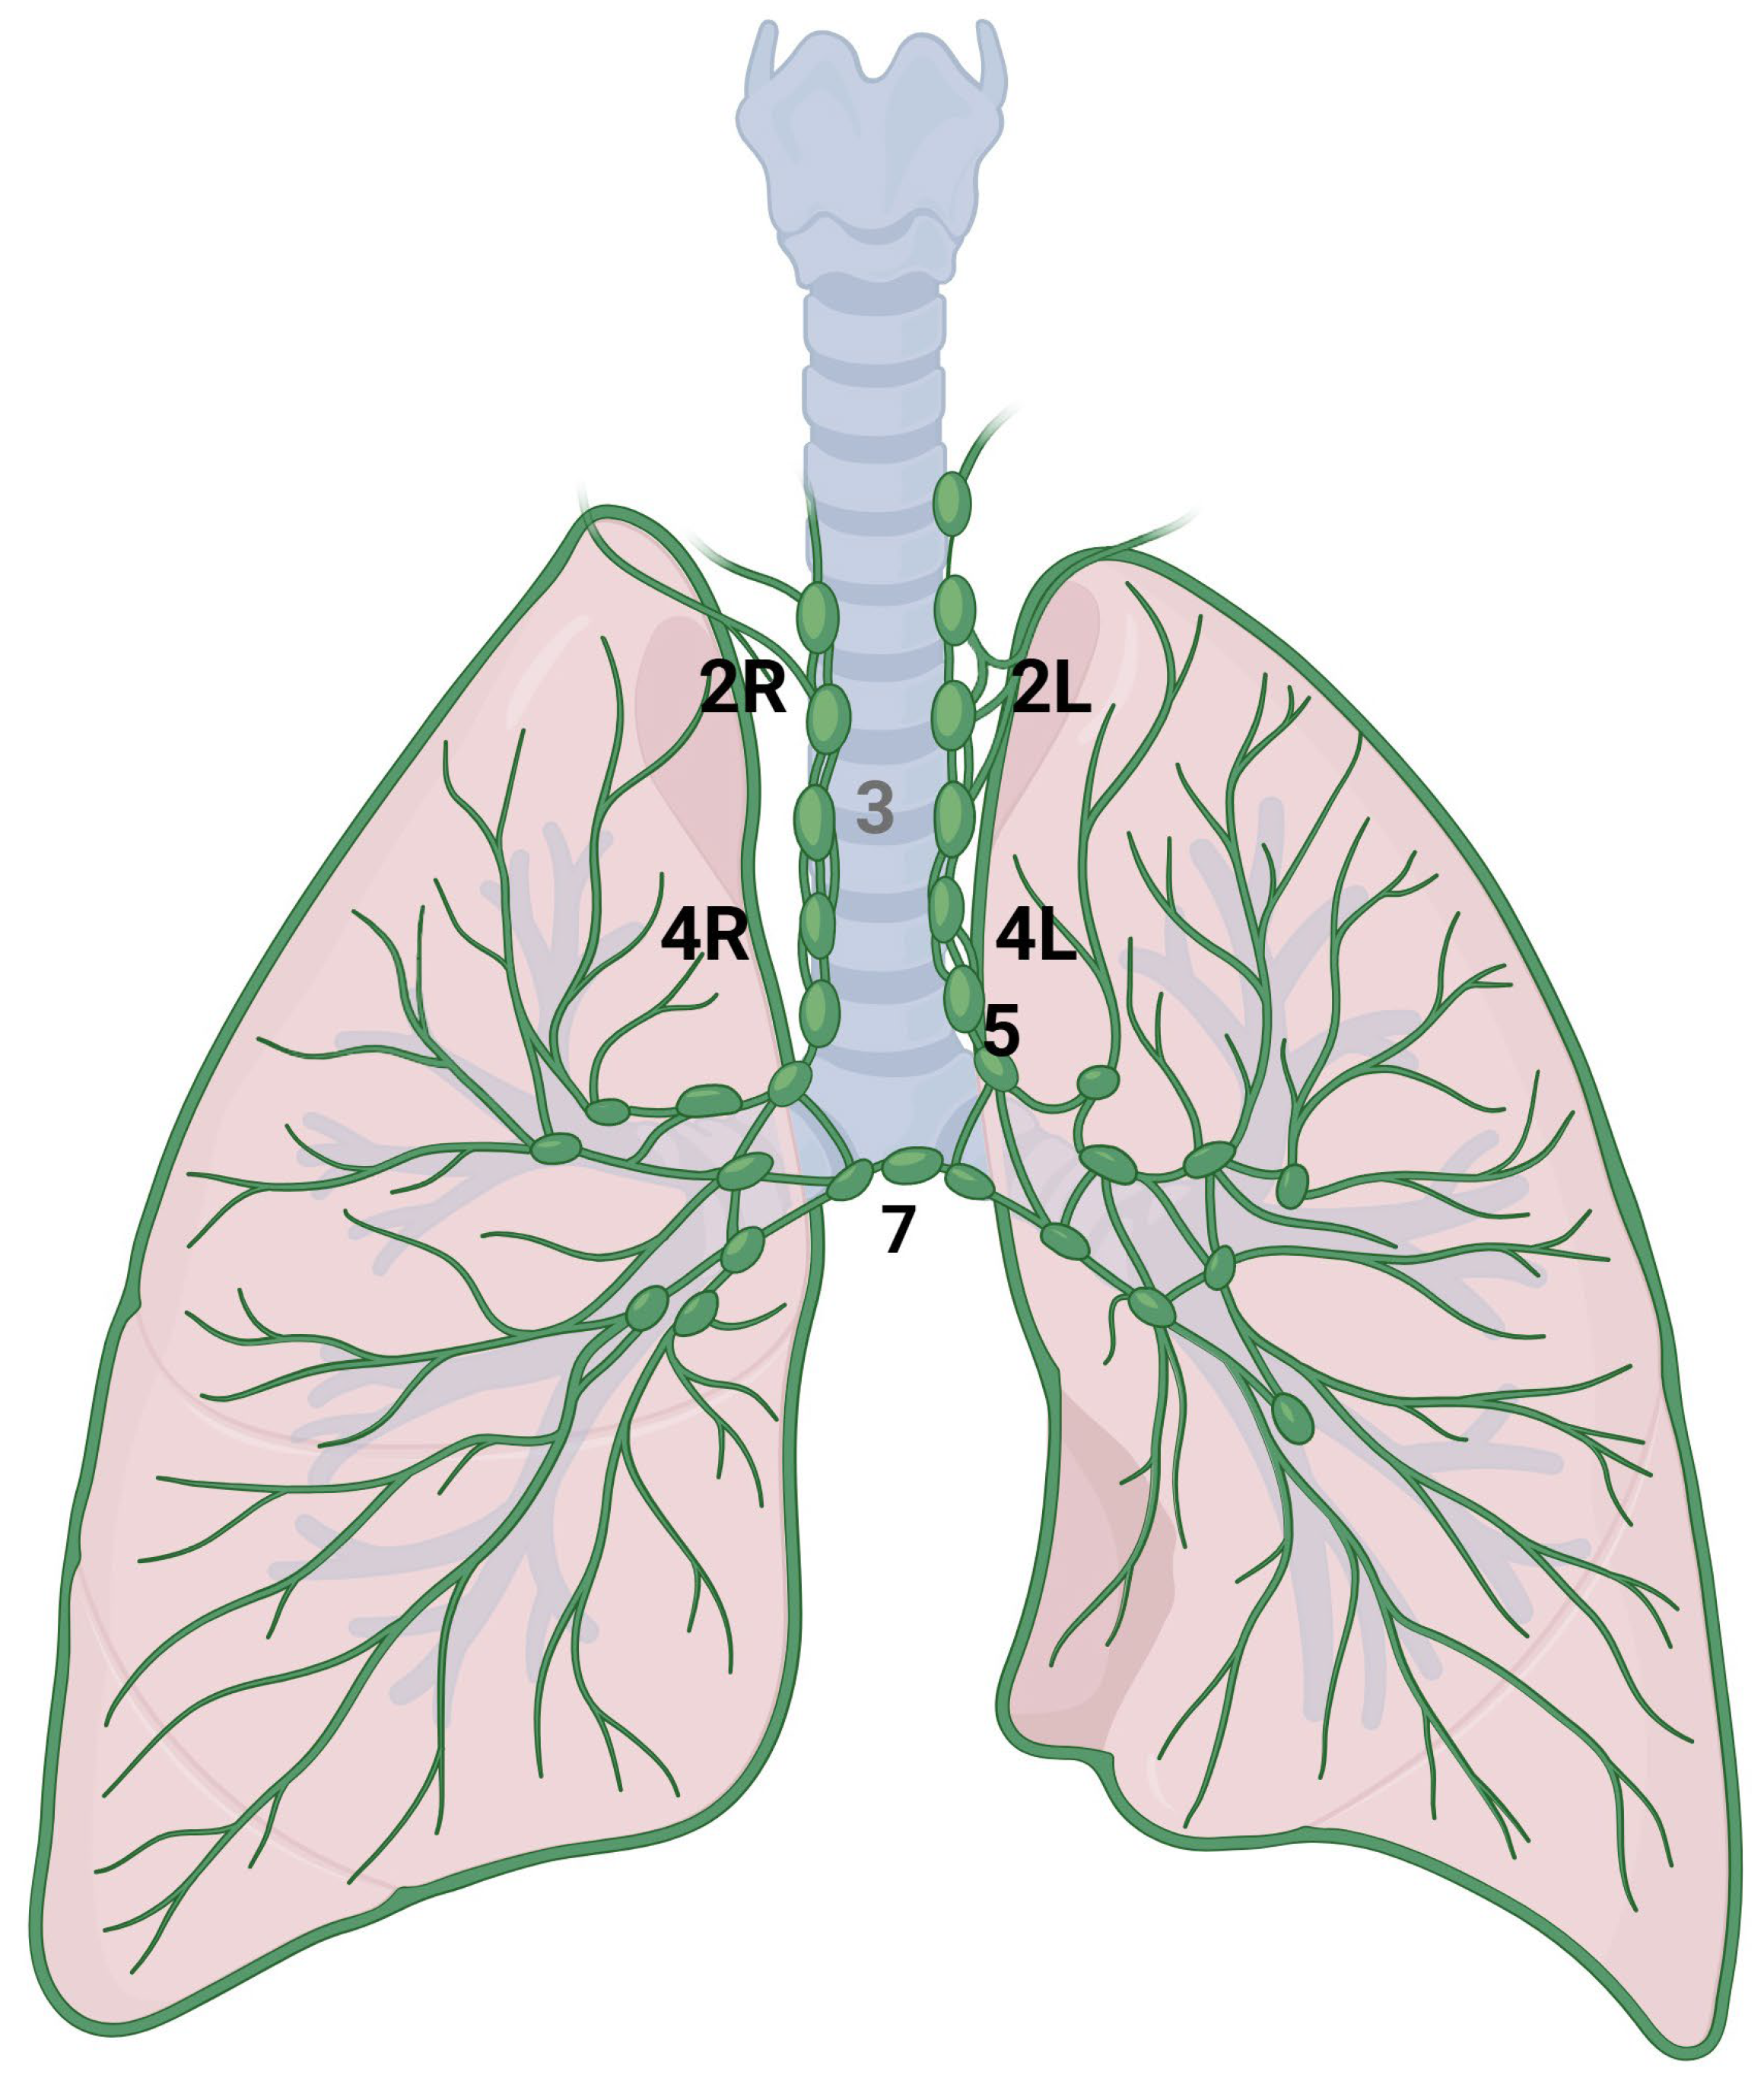

4.1. Anatomy

4.2. Imaging

| Mediastinum | X | X | Refer to node-RADS [17] for CT imaging criteria of malignancy. PET-CT more accurate. | Consider EBUS-TBNA to make a differential diagnosis between metastatic and inflammatory enlarged LNs. | ||